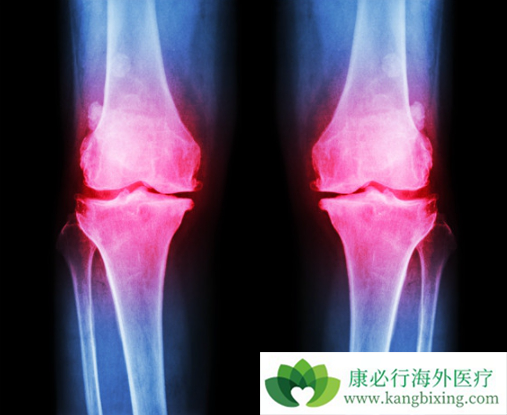

骨髓中某一种或多种的细胞增生特别旺盛,同时增生的细胞形态大致是正常的,主要有:粒细胞增生 - 慢性粒细胞白血病;红细胞增生 - 红细胞增多症;巨核细胞增生 - 原发性血小板增多症;细胞和胶原纤维 - 原发性骨髓纤维化;嗜酸粒细胞 - 慢性嗜酸粒细胞白血病。由于费城染色体和TKI靶向药物的研发,目前慢性粒细胞白血病的治疗已经有很大改观。